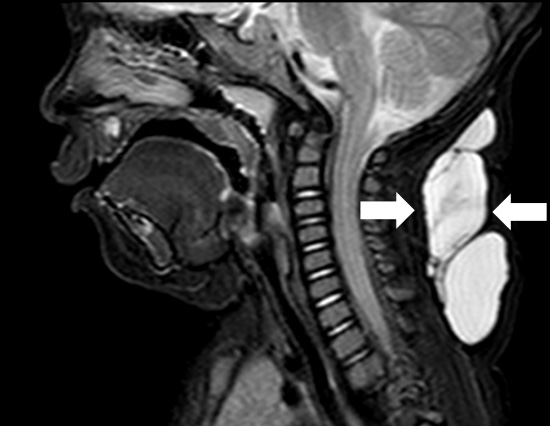

淋巴管囊肿磁共振检查

超声难以确诊的病例,或病变周围结构较复杂(如在颈部、纵隔等部位)以及位置较深(如在腹腔、盆腔等部位)治疗难度大、风险高时,往往需加做磁共振检查,更精确评估病情。当影像学检查难以诊断时,也可行诊断性穿刺,若穿刺抽出淡黄色清亮淋巴液即可诊断为淋巴管畸形,若抽出陈旧性血液结合细胞学检查可诊断为淋巴管瘤伴出血。

纵隔巨大淋巴管畸形压迫气管影响呼吸